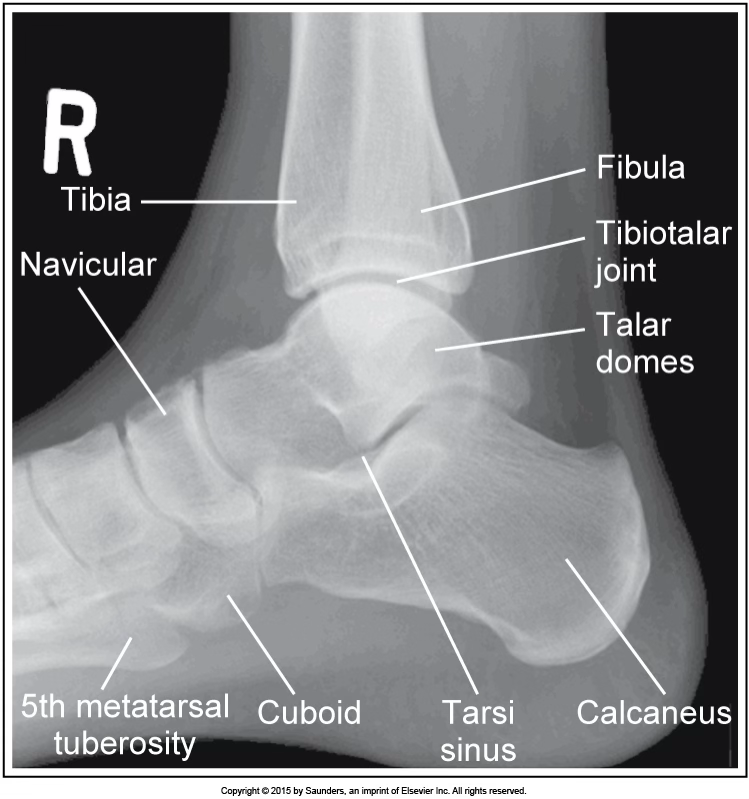

lateral ankle

accurate positioning